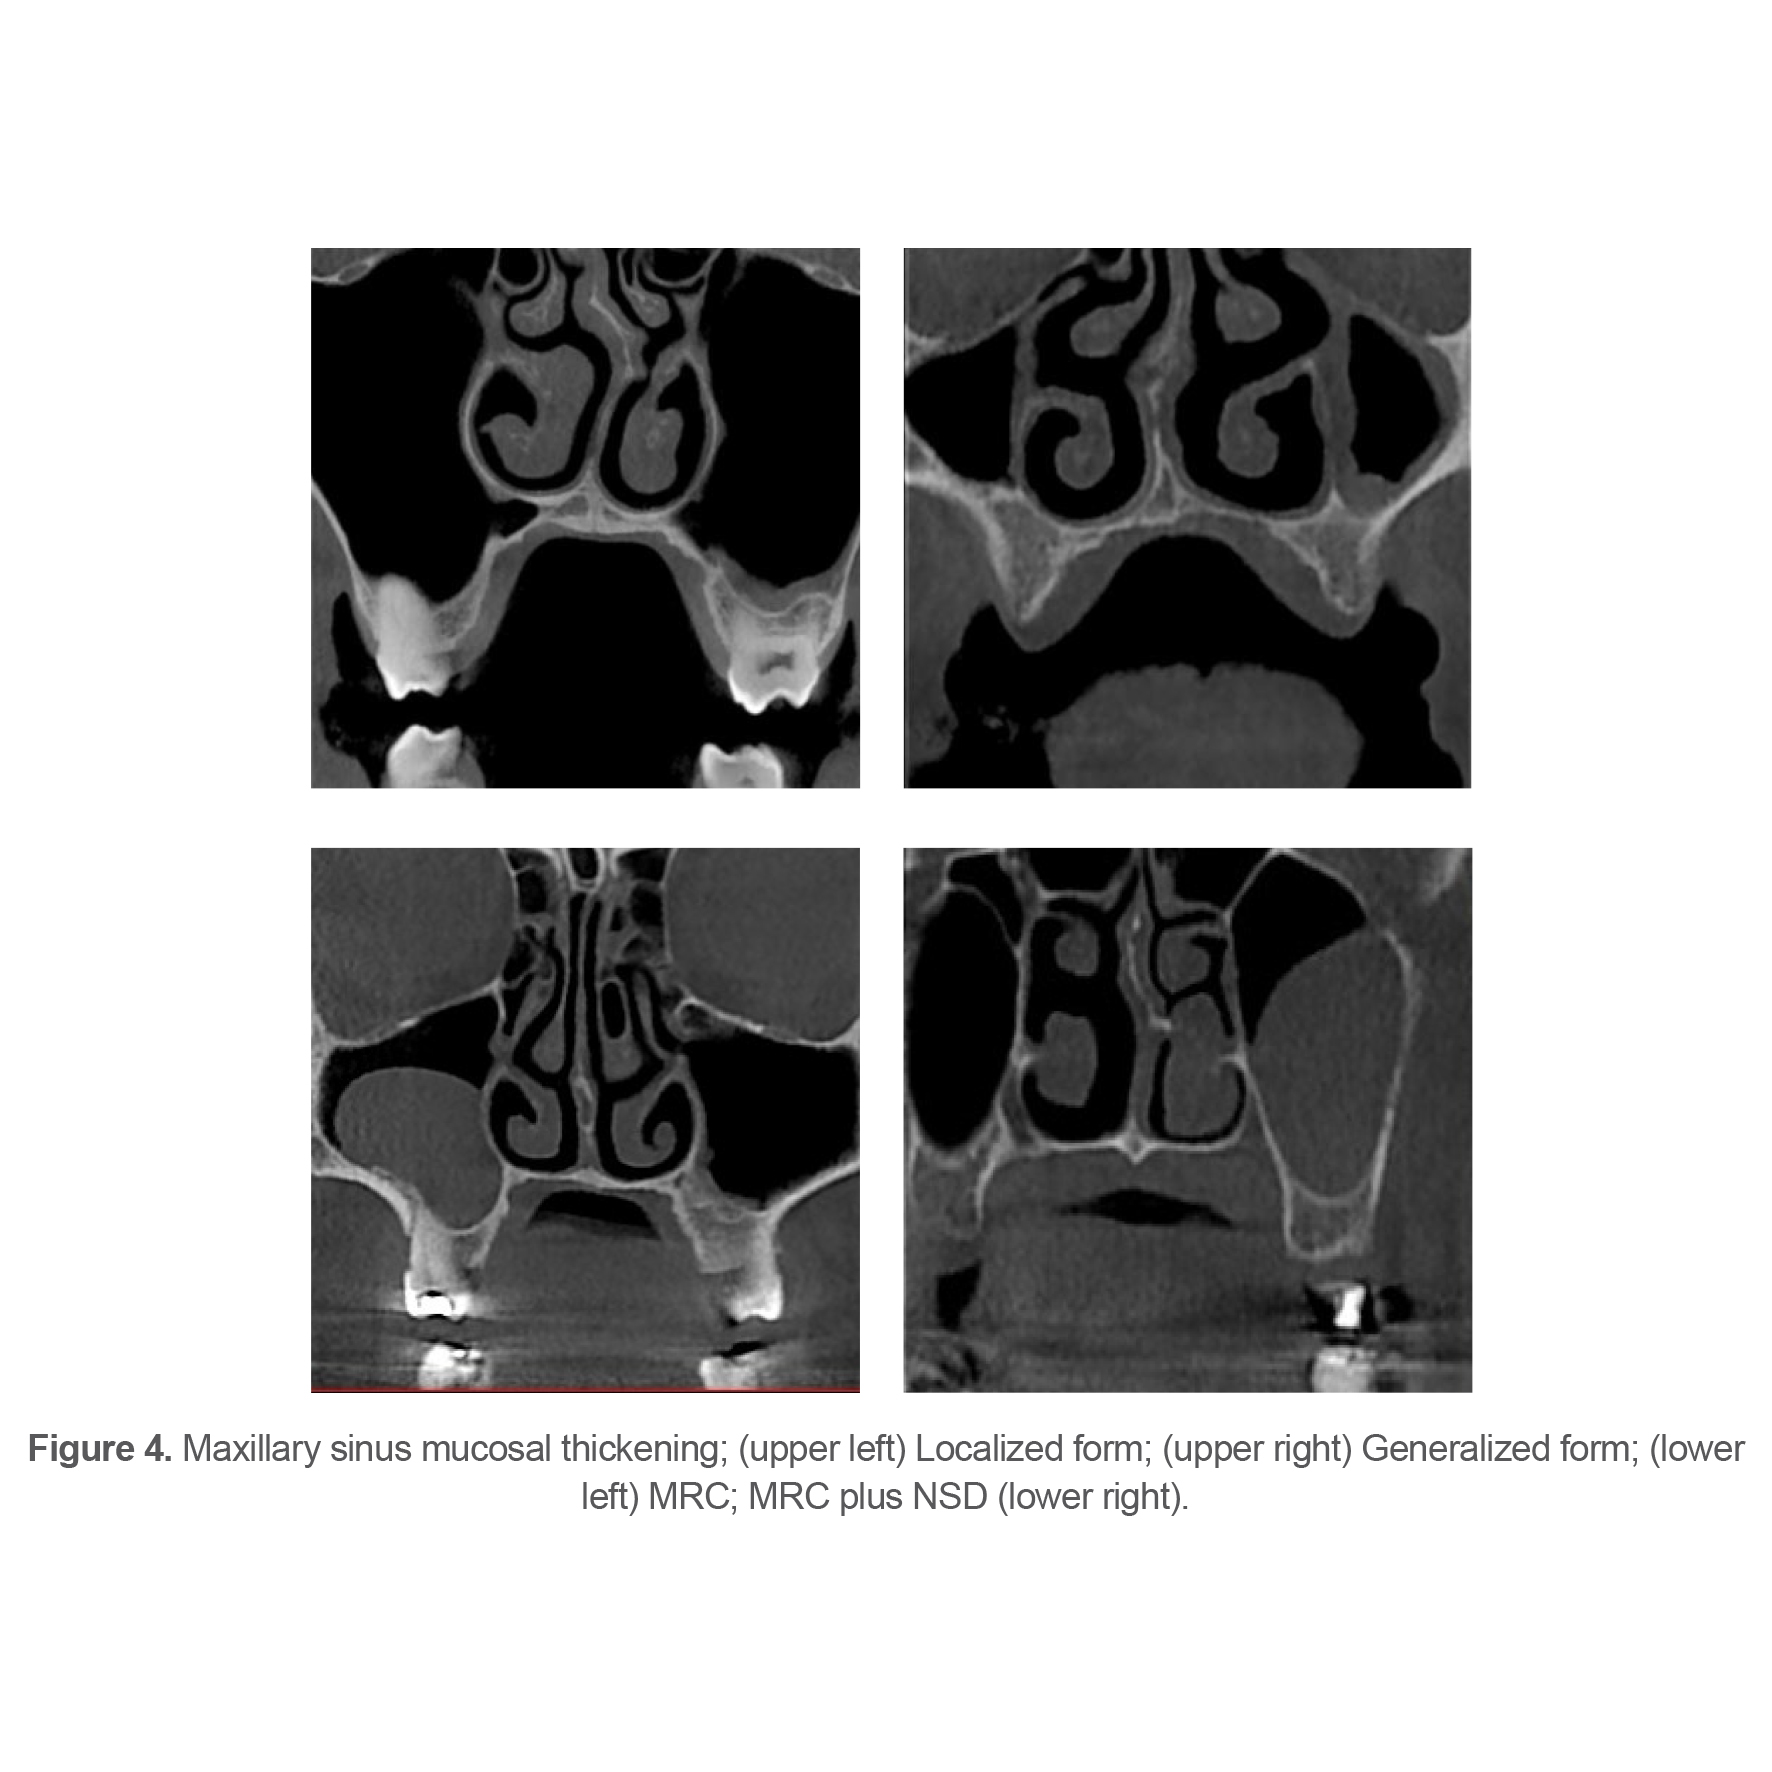

To assess the maxillary sinus MT, the distance between the sinus floor and the uppermost border of the maxillary sinus mucosa was measured on the coronal section by using the digital ruler of the software. Values > 3 mm were considered as presence of maxillary sinus MT (10) (Figure 3). Maxillary sinus MT was categorized as localized, generalized, and Mucous Retention Cyst (MRC) (Figure 4).

Figure 4. Maxillary sinus mucosal thickening; (upper left) Localized form; (upper right) Generalized form; (lower left) MRC; MRC plus NSD (lower right).